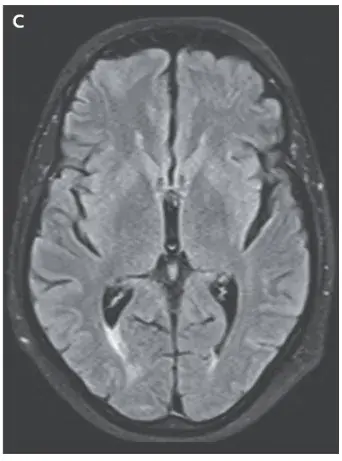

A ressonância magnética (MRI) de crânio ponderada em T2 mostrou sinal hiperintenso na substância branca cortical e subcortical, achados consistentes com **edema vasogênico** (imagens A e B). Os achados da angio-RM arterial e venosa foram normais.

Realizado retirada do medicamento (ciclosporina) e os sintomas do paciente e os achados da ressonância magnética foram resolvidos (Imagem C).